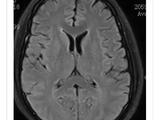

入院体格检查:体重4.3kg,头围36cm,身长52cm,神志清楚,精神差,易激惹,面容正常,前囟平软,心、肺、腹查体未见异常,注视不良,听反应迟钝,颈软,四肢肌张力增高,双侧膝腱、跟腱反射活跃,双跖反射伸性,拥抱及握持反射(-)。辅助检查:电解质、血气分析正常,肝、肾功能正常,4次血乳酸6.19-3.18(正常0.5-2.2)mmol/L,血氨正常;染色体46、XX;血串联质谱分析(MS/MS)及尿气相色谱.质谱分析(GC/MS)未见特异性异常;氨基酸分析正常。脑脊液:外观清,压力50mmH2O(1mmH2O=0.0098kPa),细胞及生化常规正常,乳酸1.54mmol/L。心电图、胸部x线片及腹部B超正常;脑电图:背景2-4Hz δ、θ波,双侧额、中央区棘波、尖波、尖-慢波;头颅磁共振成像(MRI)显示双侧丘脑、基底节区、脑干及双侧小脑、大脑半球白质区片状稍长T1、长T2信号影,于弥散加权(DWI)序列呈高信号(图2);视觉诱发电位(VEP)双侧视P100未引出,脑干听觉诱发电位(BAEP)示右侧外周段异常、左侧脑干段异常,四肢神经电图、肌电图未见异常。

入院后予口服硫胺素(维生素B1)6mg/(kg·d)及左卡尼汀、辅酶Q10等,静脉滴注能量合剂、银杏叶提取物注射液(商品名:金纳多)及脱水剂,维持内环境稳定,治疗第3天患儿易激惹状态好转,哭闹减少,吃奶、睡眠逐渐恢复正常,住院10d复查头颅MRI显示双侧基底节区软化灶,其余异常信号范围略缩小(图2),住院12d出院。出院后基因检查回报,发现患儿SLC19A3基因纯合变异:chr2:228566898(c.137T>C,p.Leu46Pro),为错义变异,其父母该位点均为杂合子(图3),该变异可能导致THTR2蛋白质功能受到影响,其致病性尚未见文献报道[参考数据库:人类基因突变数据库(HGMDPro)及PubMed];线粒体基因检测未见异常。据基因结果及临床表型确诊生物素-硫胺素反应性基底节病(BTRBGD),予口服生物素3mg/(kg·d),硫胺素增至24ms/(kg·d)。患儿3月龄时因痉挛发作半个月再次入院,复查头颅MRI示双基底节软化灶、双侧丘脑区T1稍高信号(图2),复查BAEP正常、VEP双侧P100可引出,复查血乳酸正常,予口服托比酯、静脉滴注甲泼尼龙治疗,痉挛发作逐渐减少,住院2周出院。随诊到4月龄时,痉挛发作停止,患儿吸吮困难、肌张力增高。再次出院后随访半年,精神、运动发育仍落后,无抽搐发作,复查脑电图示背景慢波,可以见到多灶性痫性放电。